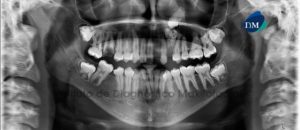

Paciente femenino de 19 años de edad, es referido al Instituto de Diagnóstico Maxilofacial – IDM (Sede Miraflores) para exámenes radiográficos para tratamiento ortodóntico y